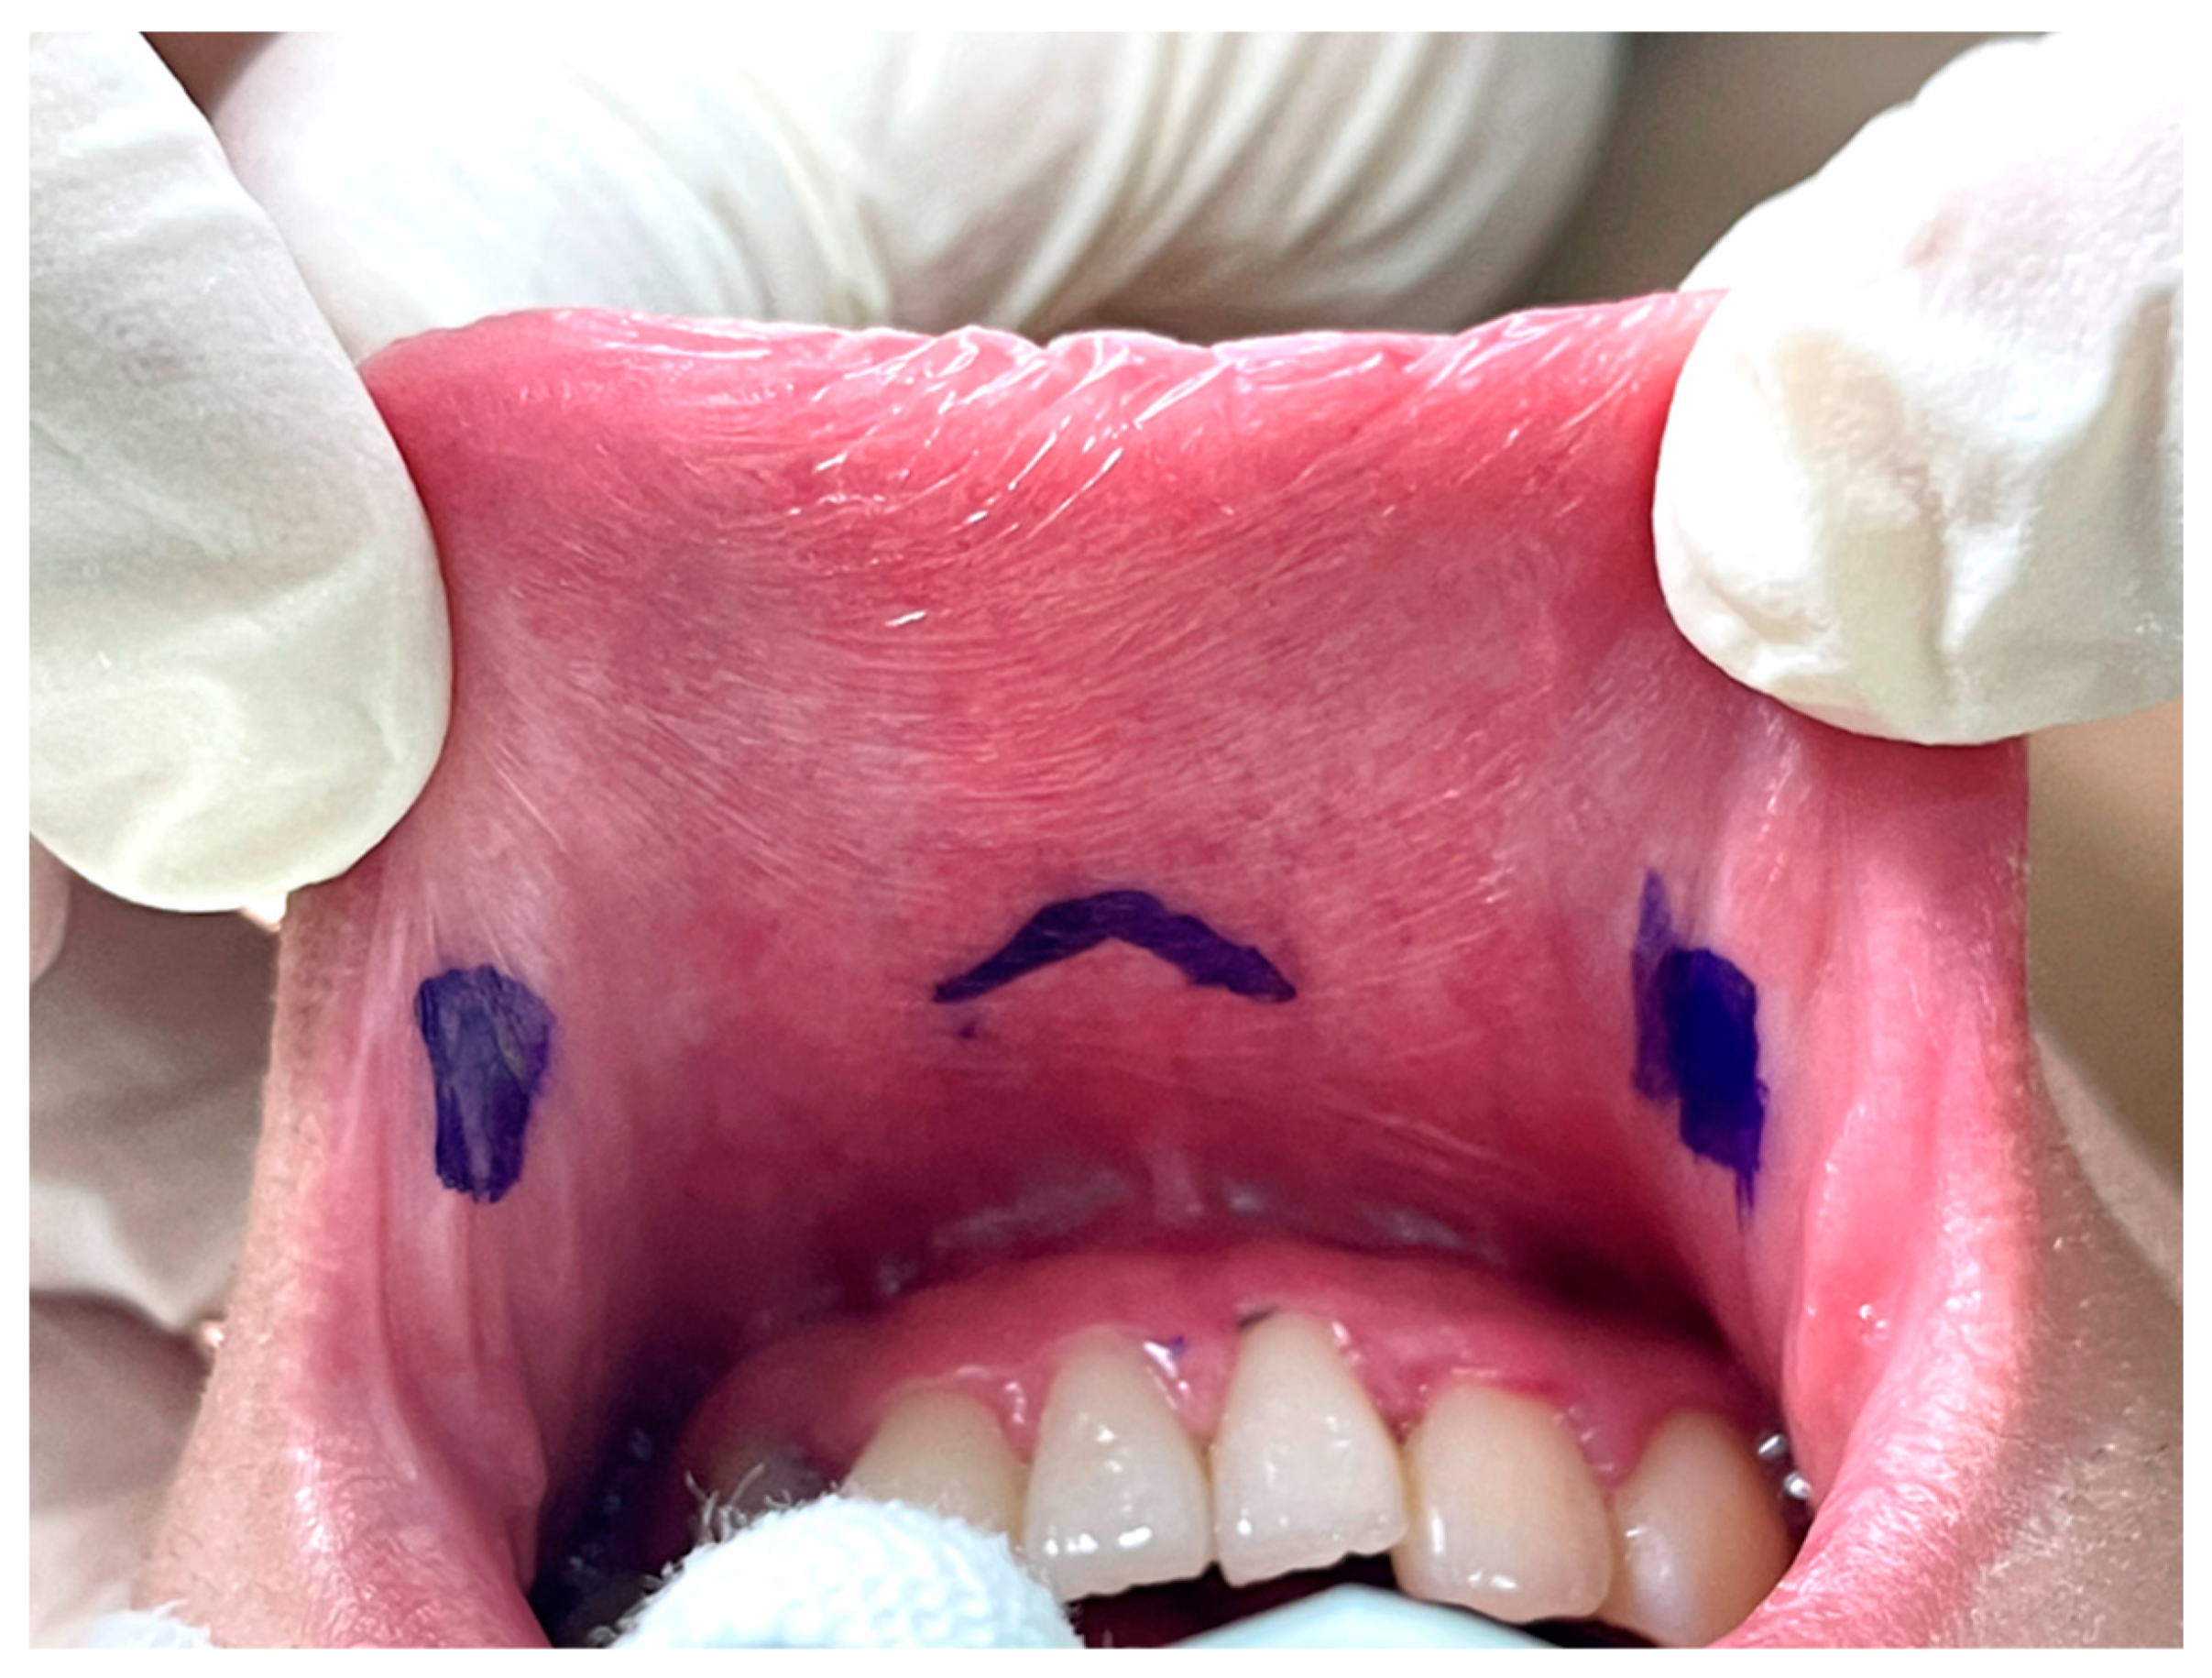

The key point of the incision design in transoral thyroidectomy is to avoid injury to the mental nerve, which might impair the sensation of the lower lip and chin [26]. In keeping with anatomical studies of the mental nerve, we adopted the concept of a safety triangle [11,27,28]. A 1.5–2-cm inverted-V shape incision was made just above the labial frenulum in the central location to avoid injury to the medial branch of the mental nerve (Figure 2) [11]. Another option is to make the central incision vertically [29]. Peng et al. [30] suggested wide mucosal dissection to fully expose the ramifications of the mental nerve and determine the optimal site for trocar insertion. Yeh et al. [31] used computed tomography simulation and 3D printing techniques to create a module that marks the location of the mental foramen and thus guides the surgeons to avoid mental nerve injury.

Figure 2.

Vestibular incision design in transoral thyroidectomy.

The other two lateral incisions (0.5 cm) were made close to the inner edge of the bilateral mouth commissure [5,32].